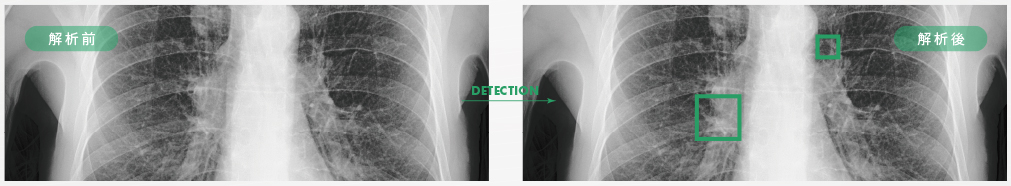

胸部レントゲン検査(肺がん診断)

当クリニックが導入したエルピクセル社のAIシステムは、AIが肺結節候補領域(※1)を検出しマーカーを表示させます。医師単独で診断する場合と比べ、検出率が9.95%向上いたします。

レントゲン画像では、空気は黒く、骨や筋肉・血液などは白く映ります。通常は黒く映る部分が白く見えた場合、それを「結節影」と呼び、肺がん、肺結核、肺炎などの可能性が疑われます。

胸部レントゲン検査で「結節影」が見られた場合は精密検査によって確認する必要があります。